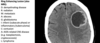

Subdural on CT head

Extradural on CT head

Subarachnoid haemorrhage on CT head